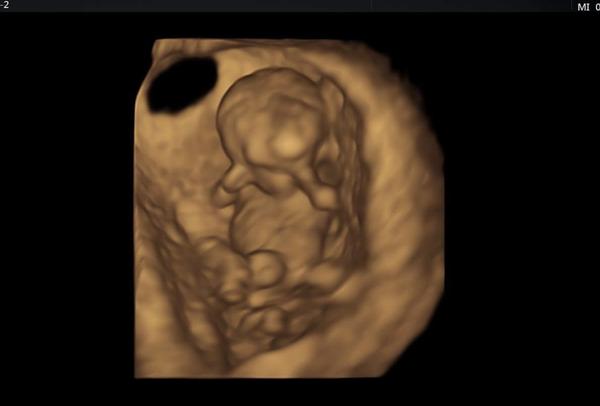

@lenulinka10 Miminko bylo mladší o 12 dní tak to dohání. Podle ultrazvuku co jsem byla dnes tak 10+5tt 😊